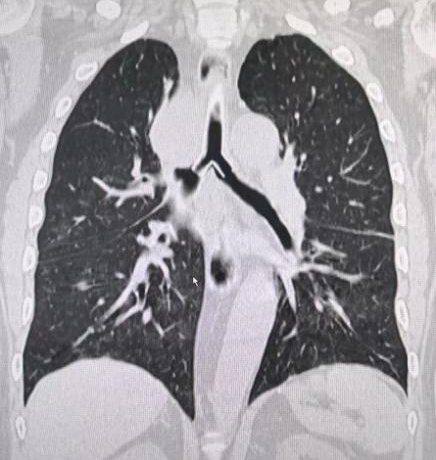

术前肺CT三维重建